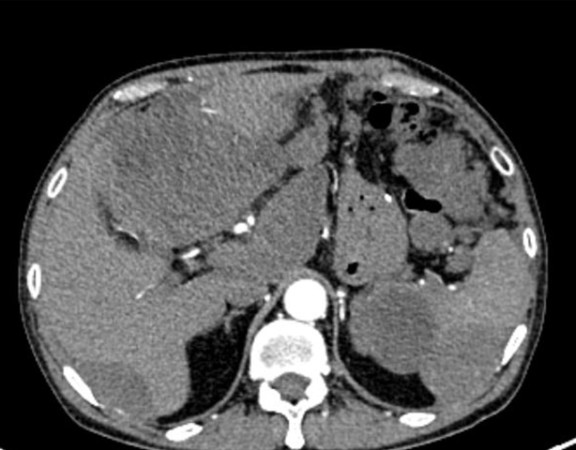

A 62 yearold gentleman presented to us with complaints of upper abdominal pain with radiation to back since 2 months. He also complained of weight loss, […]